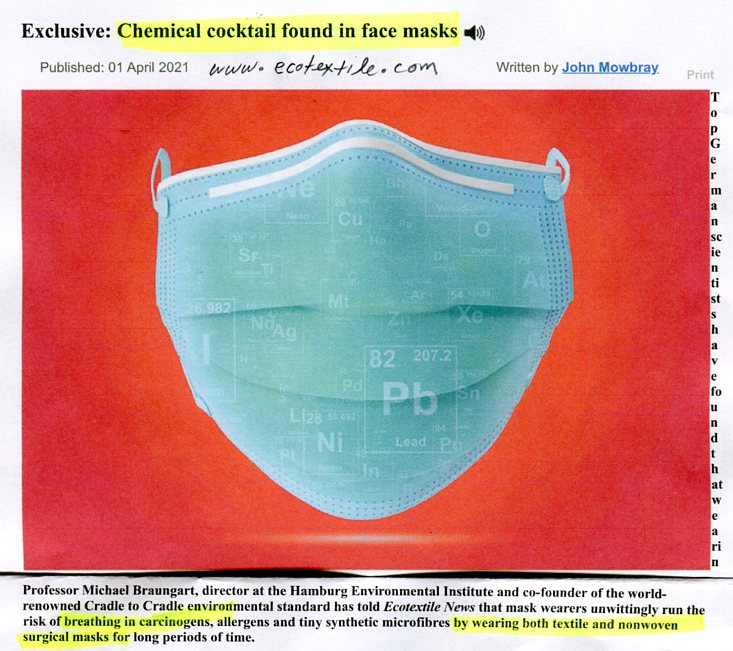

listen Dangerous Hazardous Chemicals in Face Masks

watch Nano-Worms in Face Masks Under Microscope listen

Canada recalls masks causining lung toxicity when breathing

Masks are bacteria traps on kid's breathing orifices

(gov't mandated masks is cruel form of child abuse)

Global, June 2021

watch DOCTORS SPEAK OUT TO PROTECT KIDS

(masks-isolation-tests-sanitizers-vaccines cause harm)